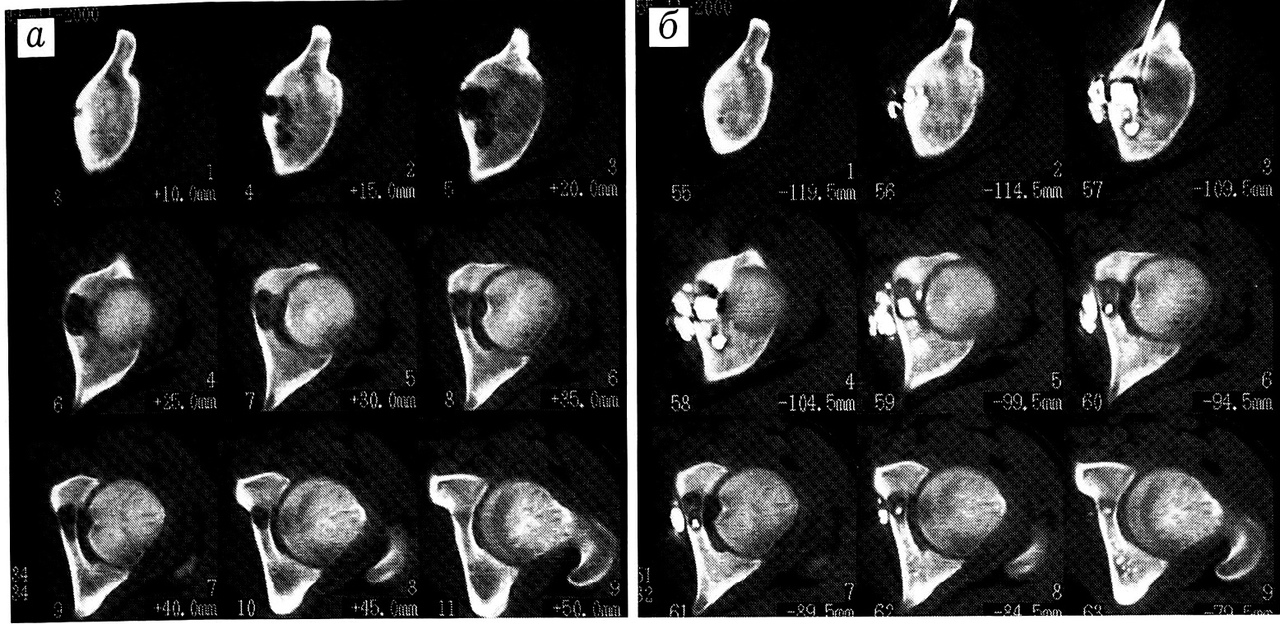

Рис. 7. Больной Ч. Интравертебральная остеоидная остеома корня правой дуги Тб позвонка. a — MPT: на Т2 ВИ определяется гиперинтенсивный сигнал от задних отделов тел и задних элементов Т5-7 позвонков; б — КТ: «гнездо» остеоидной остеомы в правых отделах дуги Тб позвонка; в — навигация «якоря» в «гнездо» остеоидной остеомы; г —контрольное обследование через 8 мес.

Больной Ч.,22 лет, обратился в ЦИТО с жалобами на боли в грудном отделе позвоночника, усиливающиеся ночью. Боли появились год назад без видимой причины. Температурной реакции, отклонений от нормы в клинических анализах крови и мочи не отмечалось. В районной поликлинике был поставлен диагноз остеохондроза позвоночника, проводилась консервативная терапия — массаж, противовоспалительное медикаментозное лечение, однако купировать болевой синдром не удалось.

При клиническом обследовании в ЦИТО выявлены выраженный грудной кифоз с вершиной на уровне Т5-7 позвонков, наличие зон резкой болезненности при пальпации в области правой паравертебральной линии и остистых отростков.

На произведенных рентгенограммах грудного отдела позвоночника в двух проекциях на уровне задних элементов Тб позвонка справа определяется участок остеосклероза с зоной просветления в центре, без четких контуров. С подозрением на остеоидную остеому больному дополнительно проведено МРТ-и КТ-исследование. Выявленные изменения расценены как интравертебральная остеоидная остеома корня правой дуги Тб позвонка.

Учитывая труднодоступность очага, под контролем КТ произведена предоперационная разметка «гнезда» остеоидной остеомы с последующей минимальной резекцией (рис. 7). При морфологическом исследовании операционного материала подтвержден диагноз остеоидной остеомы.

Пациент выписан на 4-е сутки без дополнительной иммобилизации. При обследовании через 8 мес кифосколиоз грудного отдела позвоночника отсутствует, зон болезненности в области правой паравертебральной линии и остистых отростков не определяется, признаков рецидива заболевания нет.

Представленное наблюдение демонстрирует эффективность предоперационной разметки под контролем КТ, которая позволила уменьшить объем хирургического вмешательства, снизить риск операции для пациента, сократить срок стационарного лечения и продолжительность периода реабилитации.